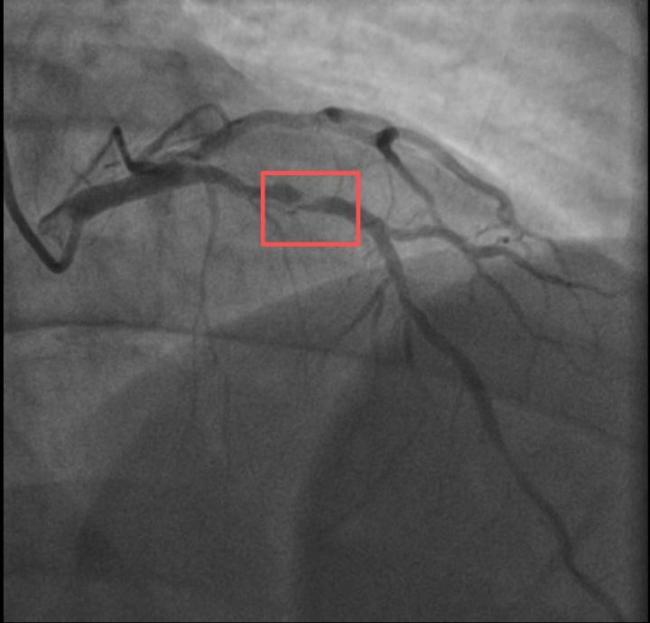

孙先生是一位羽毛球教练,身高173cm,体重约90KG。一年前,他因胸闷就诊时被查出心脏右冠中段、远端钙化斑块,以及心脏三支主要血管之一前降支中段60%狭窄。当时考虑到没有三高的危险因素(可能为早发冠心病家族史),孙先生坚信自己可以通过运动恢复健康,因此拒绝了介入治疗,只接受药物治疗。经过一年的努力,他的体重从96KG减到了90KG。然而,近日在带孩子练习羽毛球时,孙先生亲自上场挥杆仅10分钟左右,就因心前区剧烈绞痛被送进了急诊。医生分析,剧烈运动导致这位患者心脏的不稳定斑块破裂,进而造成前降支近段次全闭塞。所幸送医及时,孙先生的身体险情被化解。